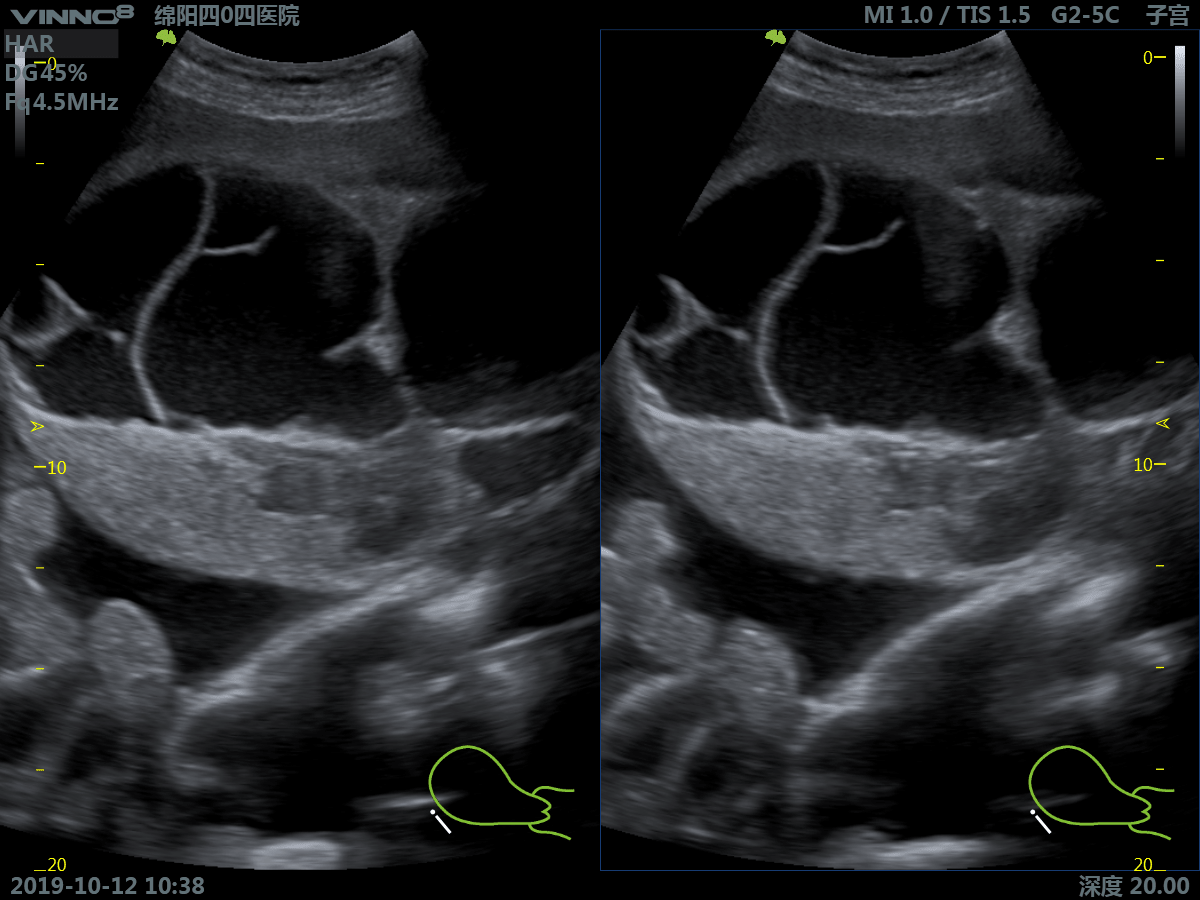

- акушерство/внутриутробное развитие

- гинекология

4. COMPOUNDING. Опция многолучевого составного сканирования (компаундинг).

8. PANORAMIC VIEW. Функция позволяет отобразить протяженную анатомическую зону на одном ультразвуковом снимке.

17. 3D. Режим получения трехмерного акустического изображения.

18. Real time 3D(4D) – B (HARMONIC) Режим трёхмерного (четырехмерного, четвертая ось - время) сканирования в реальном времени совместно с режимом тканевой гармоники.